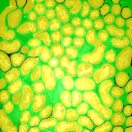

Our proposed method uses this inhomogeneity correction technique as a preprocessing step for both training and inference. Examples of original and inhomogeneity corrected images are shown in Figure 3a and Figure 3b, respectively.

The first row in Figure 3 displays an original microscopy image (), its inhomogeneity corrected version (), and manually delineated groundtruth (), respectively. For brevity we have omitted the superscript in the notation. The second row shows segmentation results of various 3D methods such as 3D region-based active contours [10] (3Dac), 3D active contours with inhomogeneity correction [11] (3DacIC), and 3D Squassh presented in [12] (3Dsquassh). Similarly, the third row portrays various segmentation methods particularly designed for tubular structure segmentation such as ellipse fitting method presented in [15] (Ellipse Fitting), the Jelly filling method in [20] (Jelly Filling), and tubule segmentation using steerable filter [21] (Steerable Filter). Finally, the last row shows segmentation results of our proposed CNN architecture without inhomogeneity correction [27] (2DCNN) and with inhomogeneity correction (2DCNNIC).